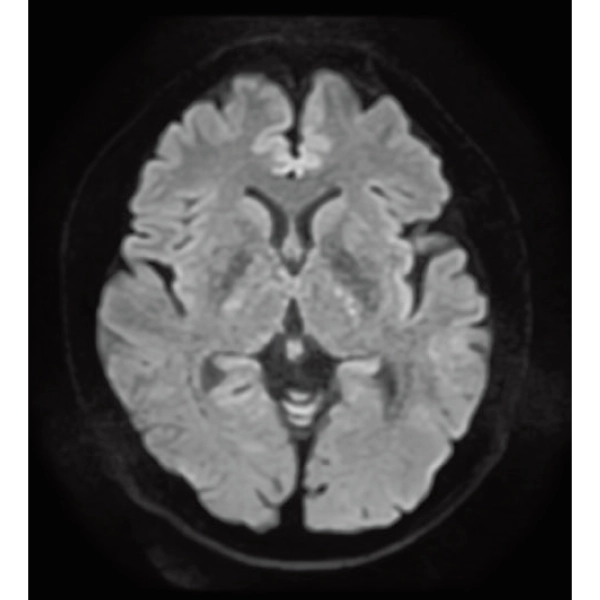

DWI, 0:36

RADAR:Body movement suppression technology for those who cannot hold still

T2*WI RADAR, 2:34

T2WI FatSat Respiratory gating RADAR, 2:16